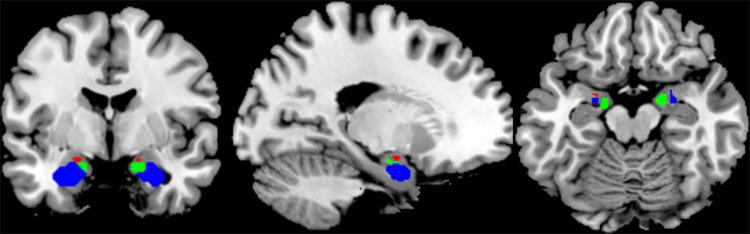

Compared with the NAD group, the AD group had a higher GABA receptor MGPS. AD patients exhibited a negative correlation between the MGPS and FC of the right centromedial (CM) subregion, and the right middle frontal gyrus (MFG). A negative correlation was also observed between the MGPS and anxiety/somatic symptoms. More importantly, the right CM and right MFG connectivity mediated the association between the GABA receptor MGPS and anxiety/somatic symptoms in patients with AD.

与NAD组相比,AD组的GABA受体MGPS更高。AD患者的MGPS与右侧中央内侧(CM)亚区和右侧额中回(MFG)的FC呈负相关。MGPS与焦虑/躯体症状之间也观察到负相关。更重要的是,右侧CM和右侧MFG连接介导了AD患者GABA受体MGPS与焦虑/躯体症状之间的关联。

结论

右侧MFG和右侧CM亚区之间FC的降低介导了GABA受体MGPS与AD之间的关联。